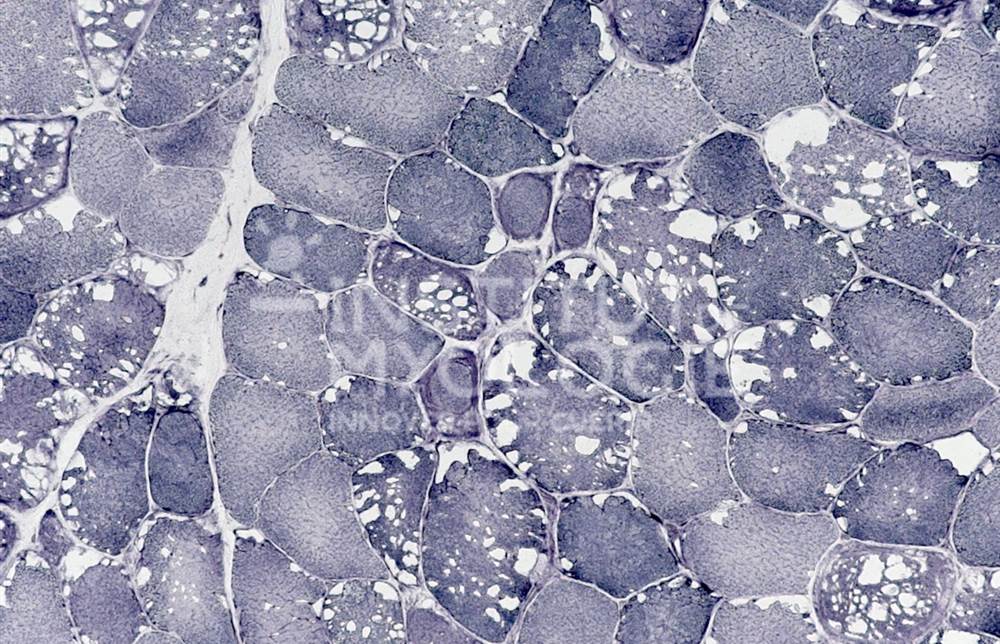

Welcome to the Muscle Atlas, the first database of muscle images designed to facilitate research, diagnosis and knowledge in the field of neuromuscular pathologies. Our vast collection includes more than 6,416 images of muscle biopsies from patients with various diseases and animal models, which may or may not be undergoing treatment. Each image is characterised according to the specific condition and corresponding stage of the disease.